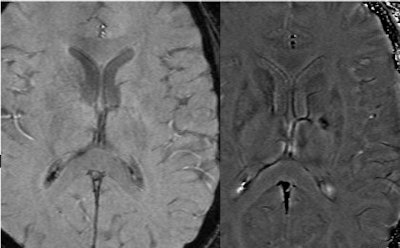

One potential application for SWI is in Alzheimer's disease and vascular dementia. A longitudinal study done in conjunction with Loma Linda University in Loma Linda, CA, has revealed a propensity of microbleeds in a major fraction of subjects with mild cognitive impairment. When many microbleeds were present at the start of the study, these patients usually progressed to become progressively impaired or dementia cases. Several ongoing studies around the world are focusing on detecting microbleeds as a marker for aging and dementia. This work by the Loma Linda group -- under the direction of Dr. Wolff Kirsch, with analysis by the Wayne State group -- may be the first of its kind to successfully demonstrate SWI as a surrogate marker for potential vascular dementia based on microbleed detection.

| SWI and aging: A connection with cerebral amyloid angiopathy. These SWI images from a 1.5-tesla scanner show a growth in the number of microbleeds over nearly two years. It is believed that these may be caused by cerebral amyloid angiopathy. This particular subject went on to develop progressive cognitive impairment (Alzheimer's disease). Image courtesy of E. Mark Haacke, Ph.D., Wayne State University, Detroit, and Dr. Wolff Kirsch, Loma Linda University, Loma Linda, CA. |